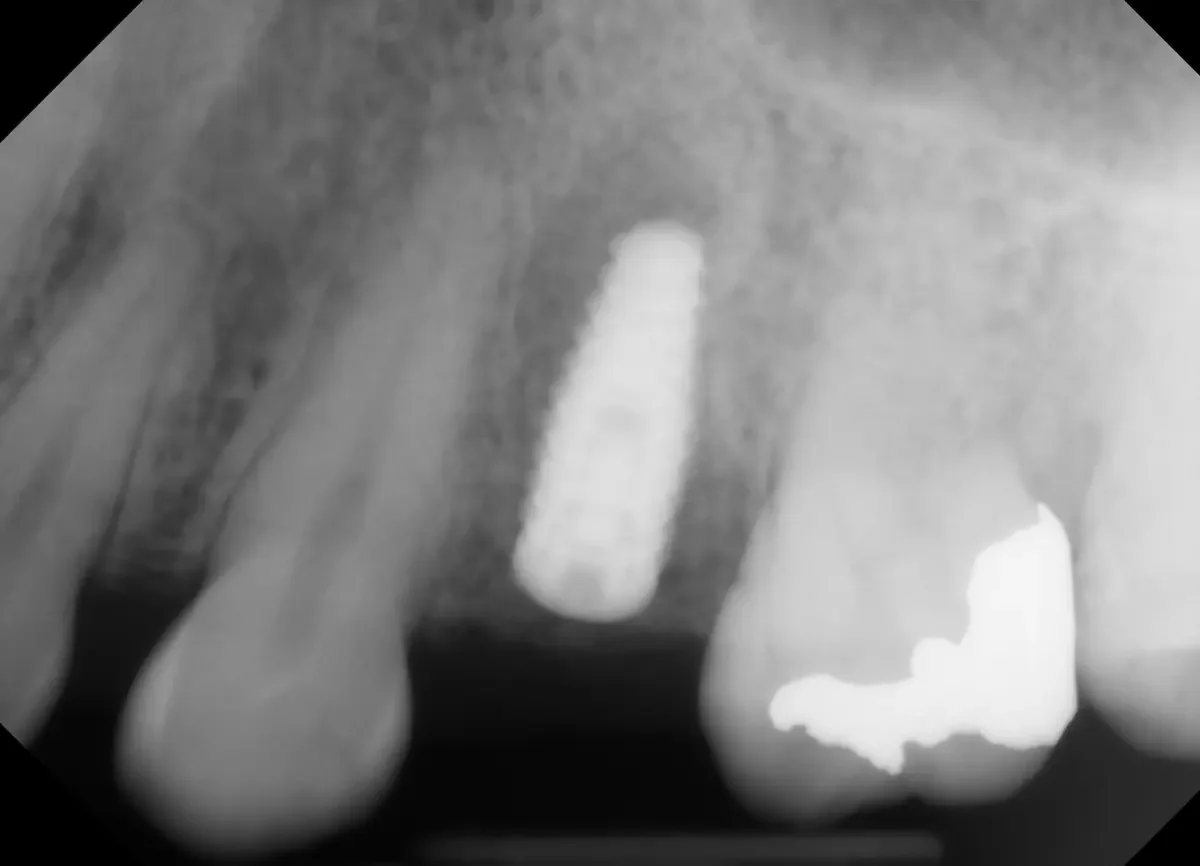

After the bone graft. Notice where the roots used to be, the socket appears filled with bone particulate.

✅ Goal: preserve ridge volume, gum contour, and future implant site quality.

From here, the body takes over — blood flows into the bone graft and forms a clot- eventually forming new bone inside the socket over the next several weeks.